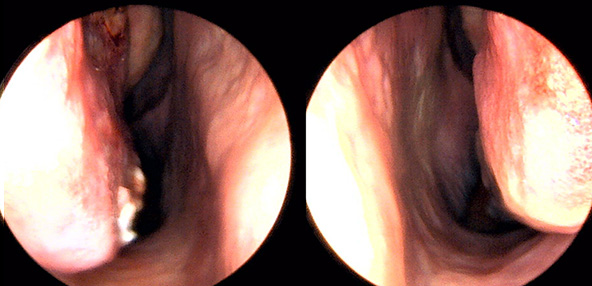

※ 비중격 비염 수술 후 생길 수 있는 부작용으로는 출혈, 감염, 염증이 있을 수 있습니다.

본 사진은 의료기관에서 진료를 본 환자이고, 전후 사진 인물이 동일인이며,동일조건에서 촬영이 되었습니다.